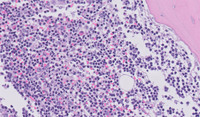

Figure 2:CLL with Trisomy 12-H&E

Bone marrow core biopsy demonstrates 90% cellular marrow extensively involved by diffuse lymphoid infiltrate of CLL cells.  Image at the top right shows vague nodular structure consistent with growth center.  At higher power, the lump chromatin and small cytomorphology of CLL cells is apparent.  At the image in the bottom left, a normal megakaryocyte can be seen towards the right side.